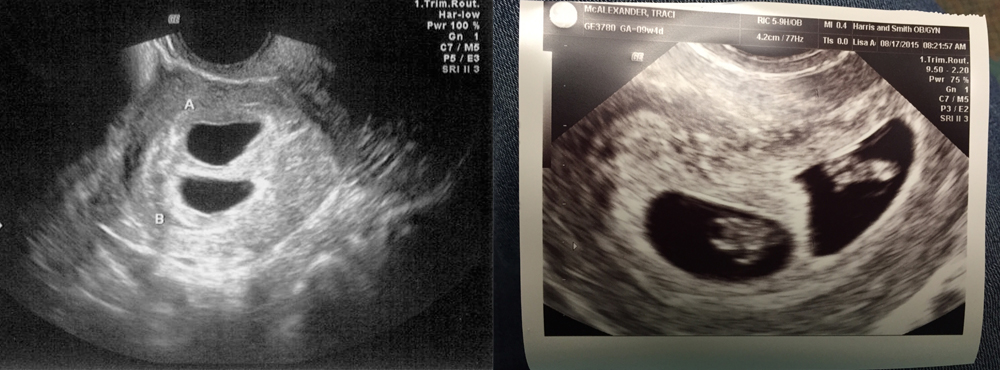

Фотографии на ранних этапах беременности